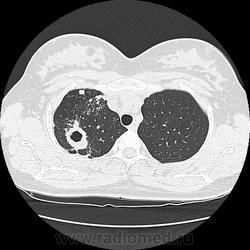

Ага, сначала вот эта с каверной пришла 12.05, а потом с туберкуломами 19.05 с интервалом в неделю, закон парных случаев, обе только родили, род.дом в панике, я в шоке

В том то и дело, что анамнез скудный, жалоб нет или врала, жила себе поживала девушка, забеременела, родила, а в правом легком "дырка".